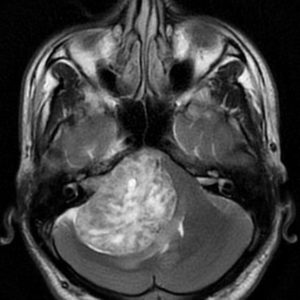

U dây VIII

Lượt xem: 132» 24-11-2018 -

U dây VIII

Lượt xem: 130» 24-11-2018 -

U dây VIII

Lượt xem: 153» 24-11-2018 -

U dây VIII

Lượt xem: 147» 24-11-2018 -

U dây VIII

Lượt xem: 117» 24-11-2018 -

U dây VIII

Lượt xem: 149» 24-11-2018 -

U dây VIII

Lượt xem: 143» 24-11-2018 -

U dây VIII

Lượt xem: 158» 24-11-2018